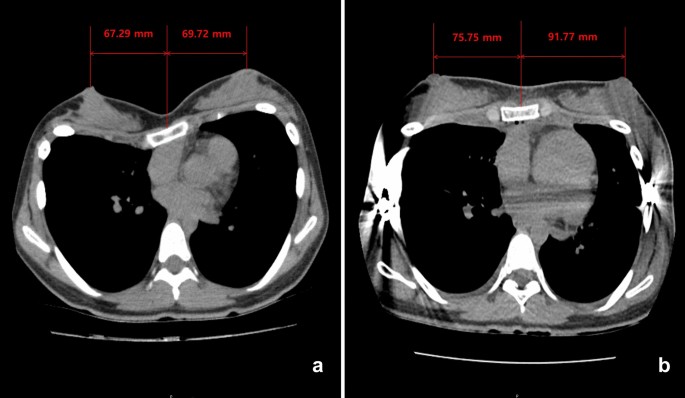

Because the breast strabismus causes a diminished intermammary distance with strabismus of the nipple-areola complexes, reposition of the breasts to an aesthetically acceptable position in women pectus excavatum patients following Nuss procedure is seemed to show increasing the intermammary distance. However, there have been no studies of properly quantified intermammary distance changes before and after pectus excavatum repair in women pectus excavatum patients. Because the breast is a three-dimensional structure, that shape can be expressed with a variety of indicators. Although simple numerical values are insufficient as a means of the breast shape expression, the authors quantified the pre- and postoperative changes in the distance between nipples by measuring the distance between them on the chest CT sections (Fig. 2).

Based on chest CT, we used the Picture Archiving Communication System (PetaVision, Seoul, Korea) to measure the distance between the sternal midline and the patients’ nipples on the left and right sides. We calculated the distance between the nipples by adding the right and left distances together (Fig. 3).